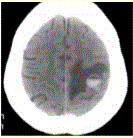

问题 患者女,55岁,右侧肢体无力3d。头颅CT显示如下图。 可能的诊断为(提示2d后复查,CT显示如下图。)

选项 A.急性脑血肿 B.转移瘤伴出血 C.胶质瘤伴出血 D.少枝胶质细胞瘤伴出血 E.血液系统病变伴脑出血 F.脑脓肿 G.血管畸形伴出血

答案 ABCEG